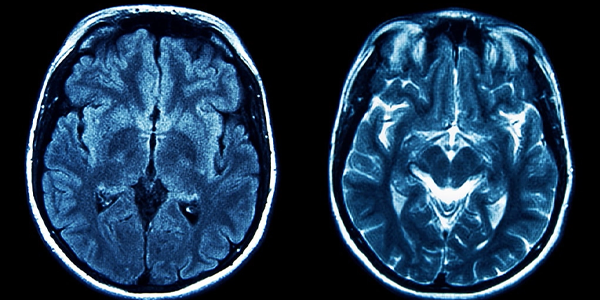

Beyin MR Türleri

Farklı amaçlar için farklı beyin MR türleri kullanılabilir:

• İlaçlı Beyin MR: Daha önce bahsettiğimiz gibi, ilaçlı MR'da damar yoluyla verilen bir kontrast madde kullanılır. Bu madde, dokuların ve organların MR görüntülerinde daha net bir şekilde görünmesini sağlar. İlaçlı beyin MR, tümörleri, enfeksiyonları ve damar hastalıklarını görüntülemek için özellikle yararlıdır.

• İlaçsız Beyin MR: İlaçsız beyin MR, kontrast madde kullanılmadan çekilir. Bu yöntem, beyin yapılarının genel bir değerlendirmesini yapmak, kanama, inme ve diğer durumları teşhis etmek için kullanılabilir.

• Fonksiyonel Beyin MR (fMRI): fMRI, beyindeki kan akışını ölçerek beynin hangi bölgelerinin aktif olduğunu gösterir. Bu yöntem, beyin fonksiyonlarını değerlendirmek ve konuşma, hafıza ve hareket gibi bilişsel süreçleri incelemek için kullanılabilir.

• Difüzyon Tensör Görüntüleme (DTI): DTI, beyindeki su moleküllerinin hareketini ölçerek beyin lif yollarının haritasını çıkarır. Bu yöntem, beyin bağlantılarını değerlendirmek ve travmatik beyin hasarı, inme ve diğer nörolojik hastalıkların teşhisinde kullanılabilir.

• MR Anjiyografi (MRA): MRA, beyindeki kan damarlarını görüntülemek için kullanılan bir MR tekniğidir. Anevrizma, damar tıkanıklığı ve diğer damar hastalıklarının teşhisinde yararlı bir yöntemdir.

Beyin_MR_G__r__nt__s___8859a1e4.webp